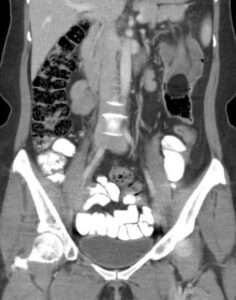

Adult Intussusception. CT Coronal Unannotated. JETem 2024